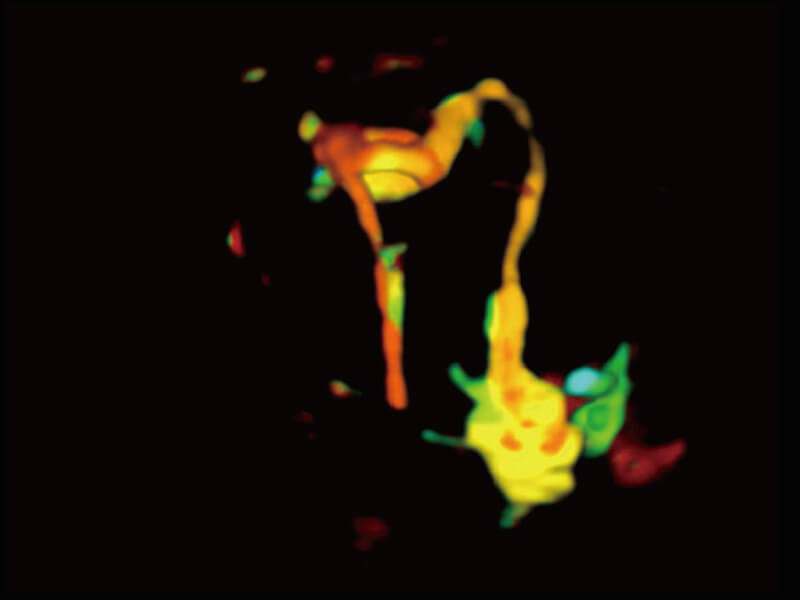

成像功能

性能优异的硬件架构,极大提升超声系统的运行效率和数据处理能力。相比以往超声成像系统,Wis+平台为您带来极快的响应速度和成像帧频,提升检查流畅度。